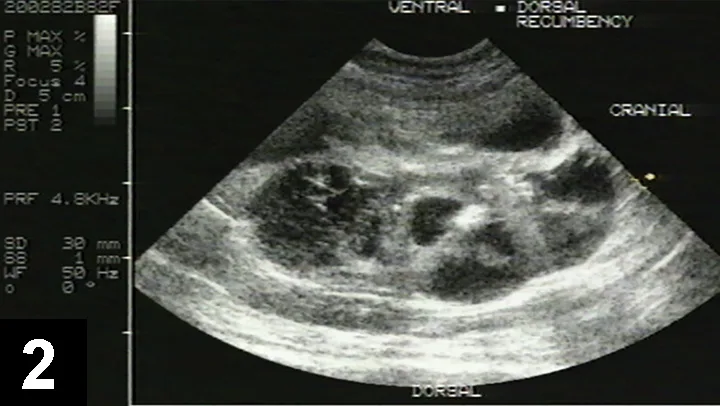

• Ultrasonography can typically identify renal cysts >2 mm in diameter (Figure 2).

• Diagnostic sensitivity of ultrasound is 91% in cats >9 months of age.27

• Phenotypic variation in cyst size and number is considerable.

• Cysts are smooth, round, or irregular anechoic structures of variable size located throughout the renal cortex and medulla and grow over sequential assessment.2,29

• Affected kidneys have indistinct corticomedullary junctions and foci of mineralization.3,29

Ultrasound image of cat kidney showing multiple round hypoechoic lesions within renal parenchyma.

FIGURE 2

Ultrasound image of a polycystic kidney in a young Himalayan cat with multiple hypoechoic cysts. Image courtesy of Dr. Susan Little